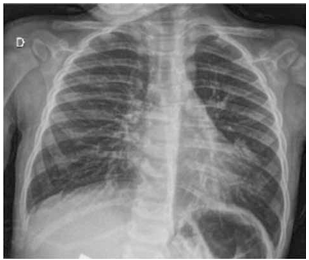

Escolar de 8 anos de idade, previamente hígido, iniciou há 10 dias quadro de febre de 38 graus, tosse, cefaleia, artralgia e odinofagia. Ficou afebril com 24 horas de evolução, porém, neste momento, é trazido ao atendimento médico por persistência dos demais sintomas e queixa de dispneia aos esforços e manchas no corpo iniciados há dois dias. Ao exame, encontra-se em bom estado geral, hidratado, corado, acianótico, anictérico, tempo de enchimento capilar de 2 segundos, FR = 40 ipm, FC = 120 bpm, SatO2 = 95%, discreta retração subdiafragmática, exantema maculopapular difuso. Orofaringe com hiperemia de mucosa sem exsudato. Otoscopia sem alterações. Murmúrios vesiculares universalmente audíveis com estertores crepitantes em base esquerda. Ritmo cardíaco regular em 2 tempos, sem sopros. Sem outras alterações no exame físico. Solicitada radiografia de tórax que revelou imagem a seguir.

(Arquivo pessoal; imagem usada com autorização)

Considerando a hipótese diagnóstica e agente etiológico mais provável, a conduta mais adequada é: